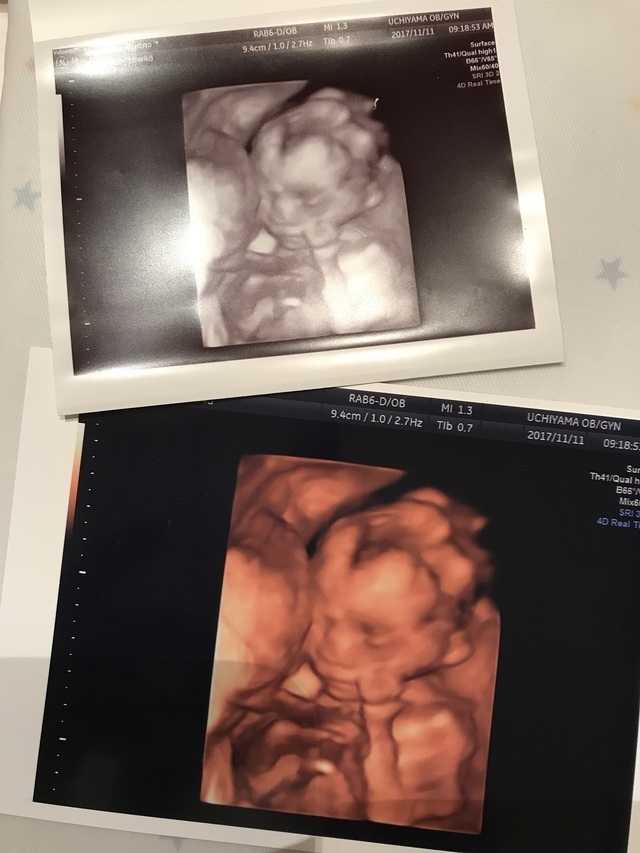

18週5日(18w5d・女の子)|ゆきち56 さん(37歳)

エコー写真撮影時のエピソード:

3Dエコーで、初めて顔を見せてくれたと思ったら、笑っているような表情だったので、思わずエコーを受けながら笑ってしまったので、気に入っています。それまでのエコー写真を見てもそんなに大きな反応がなかったパパも、この写真を見た途端に笑っていました。

18週の頃はやっと悪阻が落ち着いてきて、食事が取れるようになり、妊娠したことを素直に喜び、栄養配分に気を付けて食事内容やカロリーを考えながら生活するようになりました。